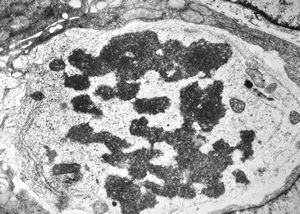

F,35y. | mitosis - intestine, celiakia